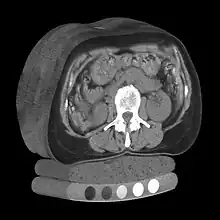

Volume rendering is a set of techniques used to display a 2D projection of a 3D discretely sampled data set, typically a 3D scalar field. A typical 3D data set is a group of 2D slice images acquired, for example, by a CT, MRI, or MicroCT scanner. These are usually acquired in a regular pattern (e.g., one slice every millimeter) and usually have a regular number of image pixels in a regular pattern. This is an example of a regular volumetric grid, with each volume element, or voxel represented by a single value that is obtained by sampling the immediate area surrounding the voxel.